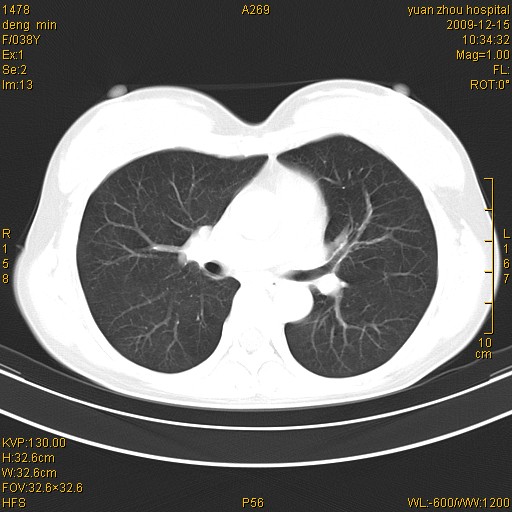

标题: CT23919:F38Y 咳嗽月余 [打印本页]

标题: CT23919:F38Y 咳嗽月余

右肺中下叶、左肺上叶舌段及左肺下叶支气管扩张合并感染。